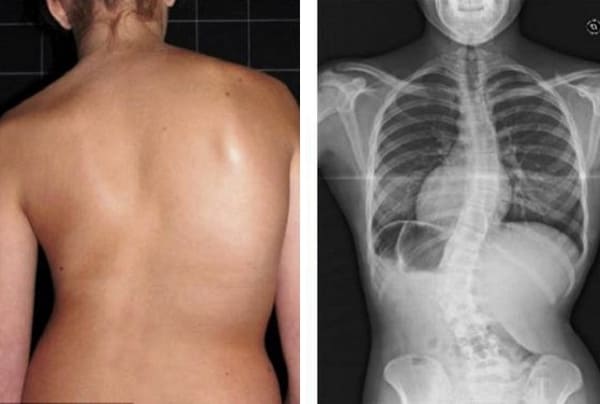

Mire estas fotografías. Esto es lo que les sucedió a todos los que ignoraron los síntomas. Hoy, estas personas están completamente sin esperanza, y muchos de ellos no tienen a quién acudir en busca de ayuda. ¿Realmente, quiere un destino así?

Atrofia y fuerte curvatura de las articulaciones de las rodillas, dolor constante y agudo incluso con los movimientos más leves.

Mujer, 62 años. Luxación grave de vértebras. Hondrodox restauró completamente la columna en 2 cursos.

Mujer, 42 años. Deformación severa de la articulación de la rodilla, rodillas cóncavas. El curso de Hondrodox requirió 2 cursos para la recuperación completa.

Hombre, 37 años. Corrección completa de la postura con Hondrodox en 1 curso.

Mujer, 51 años. Joroba de viuda y deformación de la columna. Eliminación completa de la joroba tras 1 curso de Hondrodox.